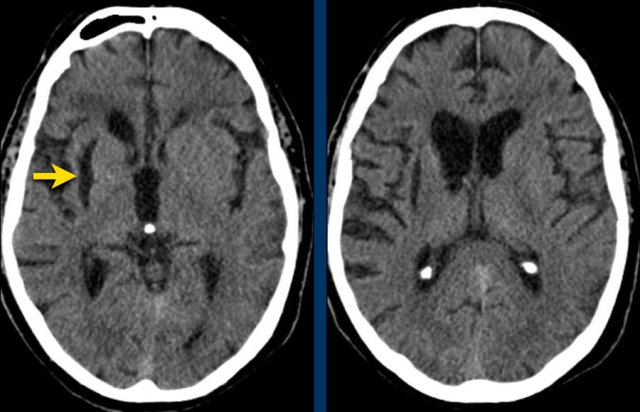

Thalamus

Bleeding in the thalamus is typically seen in hypertension.

This patient presented with hydrocephalus due to an intraventricular hemorrhage (left image).

Note the very small hyperdensity in the left thalamus, which is the origin of the hemorrhage.

Follow-up one day later (right image).

The patient  underwent surgery with placement of a ventricle drain to treat the hydrocephalus.

Note the hypodense thalamus on the left side with the persistent medially located hyperdense focus.